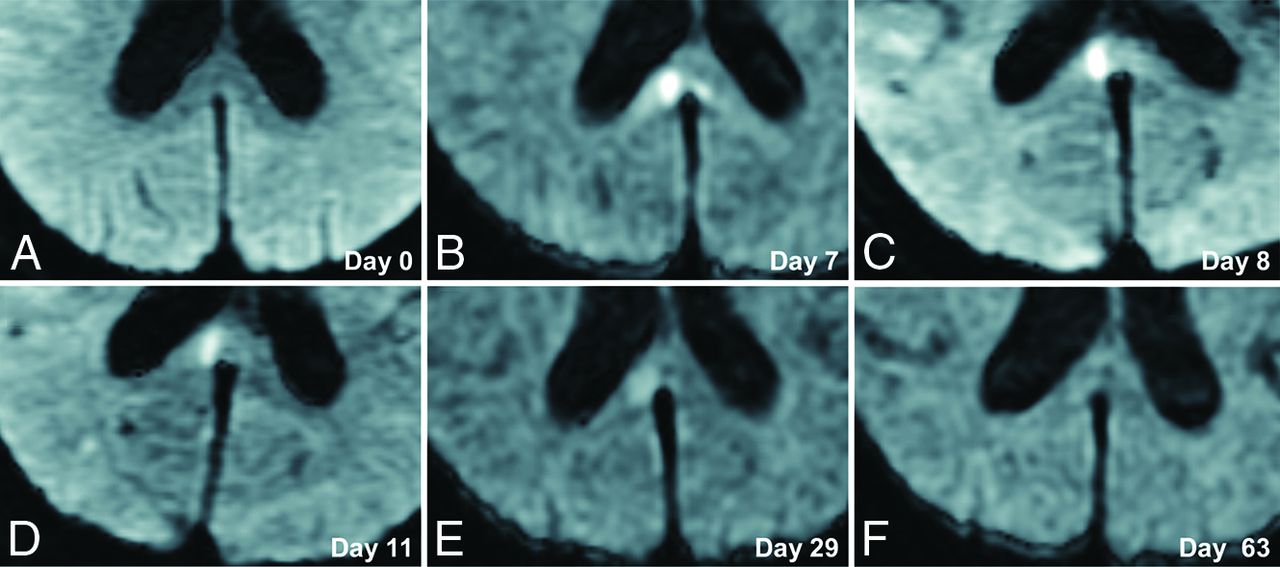

A 70-year-old woman presented with poor-grade SAH (Hunt and Hess grade 4). CT revealed Fisher group 3 SAH, and MRA demonstrated a 5-mm-diameter aneurysm on the anterior communicating artery. The patient underwent aneurysm coiling on day 2. This patient developed DCI and received regional arterial infusion of fasudil hydrochloride hydrate 3 times. She also developed hydrocephalus and underwent ventriculoperitoneal shunting. The patient had mild disorientation and was discharged home with an mRS score of 3. Although no abnormality was evident on DWI in this patient on admission (Fig 2A), a high-signal area appeared in the splenium of the corpus callosum on SAH day 7 (Fig 2B). The lesion gradually faded and had completely resolved by day 63 (Fig 2C–F). This change was thought to represent CLOCC and was also observable on FLAIR and T2WI (Fig 3).

Serial DWI in an illustrative case. A 70-year-old woman presented with poor-grade SAH due to rupture of an aneurysm (diameter, 5 mm) at the anterior communicating artery. DWI on admission shows no lesion (A). CLOCC appear on days 7–8 (B and C) and gradually resolve (D–F).